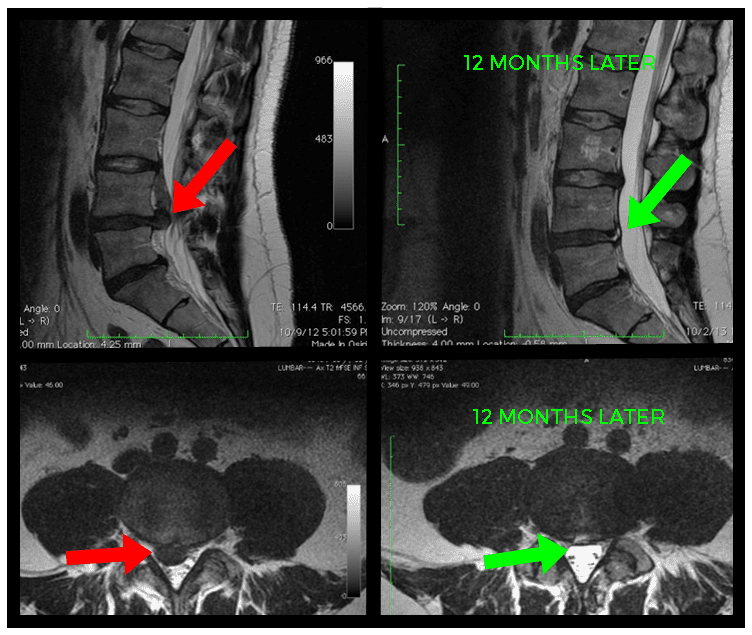

Diagnostic Imaging

Imaging techniques such as X-rays, MRI, or CT scans provide detailed visuals of the spine, allowing for the identification of abnormalities like disc protrusion. These diagnostic tools can offer valuable insights into the extent of the condition and guide treatment decisions.

Timely treatment, guided by an accurate diagnosis, is crucial in managing disc protrusion effectively. Early intervention can prevent further damage, improve long-term outcomes, and enhance the overall quality of life.